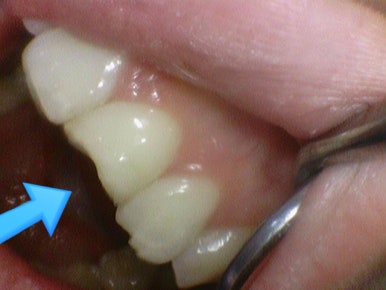

Case2.

위의 케이스 1과 동일한 분 아니냐고요?

아닙니다... 이렇게 저희 치과에 앞니가 깨진 분이 많이 오신다구요... (동의한 사진만 공개해요)